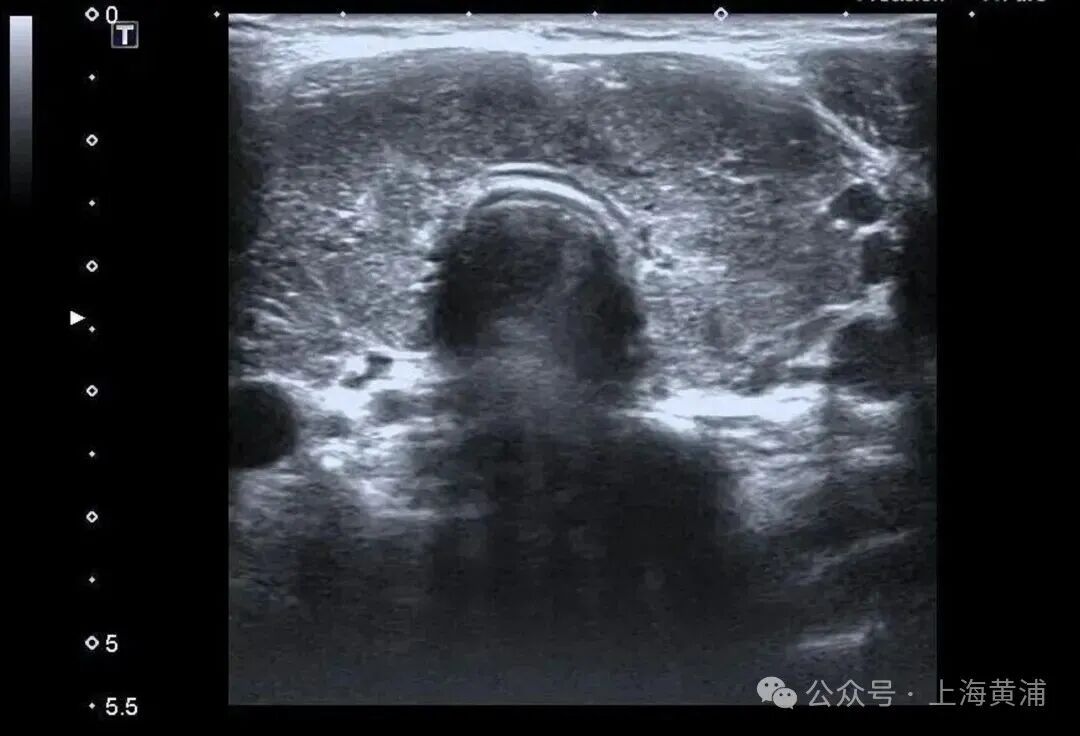

而更致命的隐患藏在她的病史里——陈女士是一位有着20年甲亢病史的患者,并且已经自行停药一年。鉴于病情危重,陈女士被紧急转入瑞金医院卢湾分院内分泌科。

入院后的检查结果显示

陈女士的身体

正被一场“激素风暴”席卷

甲状腺功能检查中,游离T3高达20.83 pmol/L(正常值3.5 - 6.5pmol/L),游离T4高达88.42 pmol/L(正常值11.5 - 22.7pmol/L),这两项核心激素都超过正常上限数倍,而本应调控它们的促甲状腺激素(TSH)却几乎测不出来,这明确证实了陈女士患有极其严重的甲状腺毒症。心脏超声结果同样不容乐观,射血分数仅有40%(正常应高于55%),这意味着心脏泵血能力大幅下降。

同时,CT检查发现她的双侧胸腔、腹腔存在积液。综合各项检查结果,医生判断陈女士患上了甲状腺危象,这是甲亢最凶险的并发症。